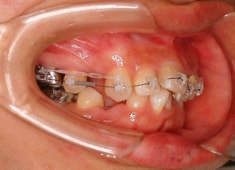

治療開始時

治療開始から1年8ヶ月後